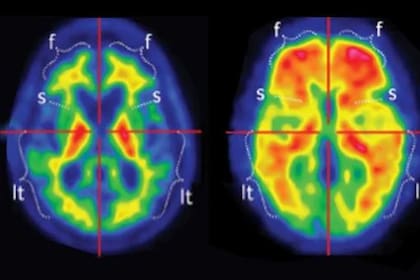

Los escáneres cerebrales de un adolescente de 19 años, considerado el paciente más joven diagnosticado con probable enfermedad de Alzheimer, revelan el impacto devastador de esta condición neurodegenerativa. El caso, descrito por investigadores de la Capital Medical University de China, sacude la comprensión tradicional de una enfermedad que suele asociarse a la edad avanzada, algo que muestra cómo el deterioro puede manifestarse con virulencia en cerebros jóvenes y sin precedentes genéticos. El joven de Beijing comenzó a experimentar síntomas a los 17 años, lo que marcó un declive que lo debilitó rápidamente.

Los exámenes de neuroimagen fueron cruciales para el diagnóstico. Una tomografía por emisión de positrones (PET) y una resonancia magnética con 18 F fluorodesoxiglucosa mostraron “atrofia del hipocampo bilateral e hipometabolismo en el lóbulo temporal bilateral”, tal y como expuso el portal SAGE Journals. El hipocampo, fundamental para la formación de la memoria, se redujo significativamente, un hallazgo confirmado por resonancias magnéticas que señalaron su reducción. Además, las cortezas parietal y temporal, esenciales para el pensamiento crítico, también exhibieron una visible reducción de tamaño.

El análisis del líquido cefalorraquídeo (LCR) del paciente proporcionó más evidencia del daño. Se detectaron niveles elevados de proteínas tau y una proporción anormal de proteínas amiloides, marcadores distintivos de la enfermedad de Alzheimer. Aunque las exploraciones PET especializadas para amiloide no mostraron una acumulación evidente, los expertos señalaron que estas exploraciones pueden tener limitaciones para detectar las etapas iniciales, por lo que las pruebas de LCR son más sensibles en esos casos.